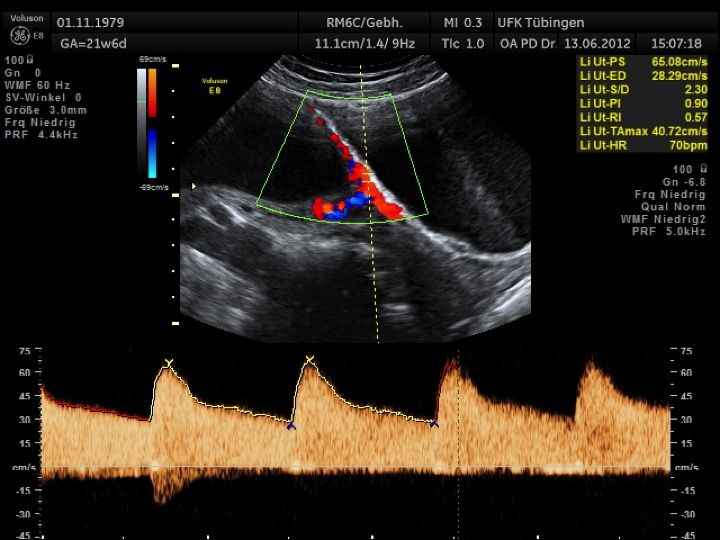

Mithilfe des Ersttrimester-Screenings kann das persönliche Risiko einer Präeklampsie bestimmt werden. Dazu wird die Vorgeschichte der Schwangeren, der aktuelle Blutdruck, das Ergebnis der Ultraschalluntersuchung (Widerstand in den Gebärmutter-nahen Gefäßen) und der Blutabnahme bei Ihnen (PAPP-A) kombiniert. Sollte das Risiko über 1:100 sein, empfehlen wir die tägliche Einnahme von Aspirin 150mg bis zu 35.SSW und eine gezielte Überwachung der weiteren Schwangerschaft.

Das Ergebnis der Ultraschalluntersuchung ist wegweisend. Dabei wird der Fet vermessen, die Organe werden untersucht und die sonographischen Marker zur Risikoberechnung für Chromosomenstörungen werden beurteilt. Das sind: die Nackentransparenzdicke, Nasenbein sowie der Blutfluss in der rechten Herzhälfte und im Ductus venosus, einem Gefäß in der Leber des Feten.